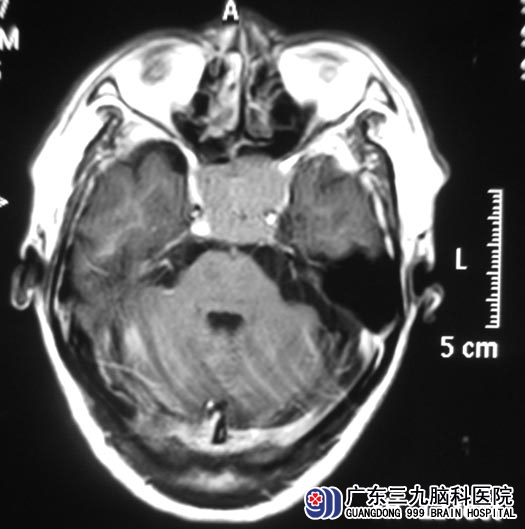

广东三九脑科医院的头颅MR检查提示:鞍区、斜坡、蝶窦部位巨大占位性病变,大小约4.61cm×2.54cm×3.63cm,内分泌检查结果提示泌乳素增高,垂体瘤诊疗中心鲁明主任考虑侵袭性垂体大腺瘤可能性大。